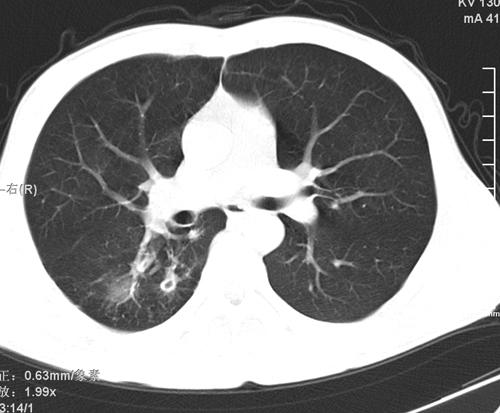

标题: CT24548:男 31 咳嗽 咯血一天 行CT检查 [打印本页]

标题: CT24548:男 31 咳嗽 咯血一天 行CT检查

ct考虑结核 但化验结果示白细胞总数 淋巴均正常,血沉7mm/h不快,请看看结核 支扩还是其他

右肺上叶尖端,后段下叶背段结核伴空洞形成

继发性肺结核伴空洞形成!

考虑右肺继发性肺结核伴空洞形成。